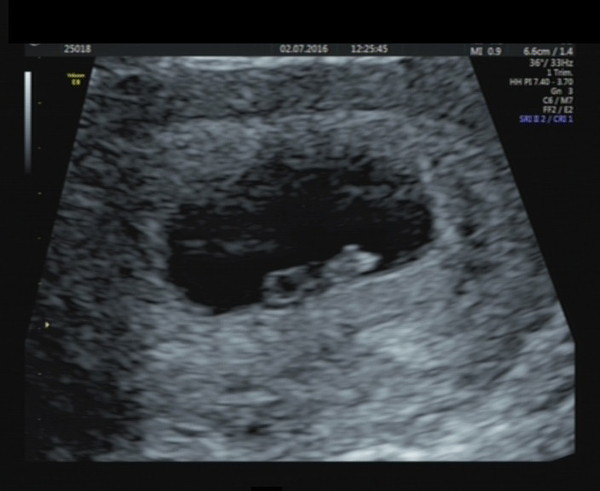

Kellz92 · 02/07/2016 17:25

Had a private scan today as a present from my mum. At my last epu scan I was 6+4 but baby only measured 5+2 today I'm 8+6 and baby bus also measuring 8+6 with a strong heartbeat x

Woohoo kellz fab news! Glad it's a good day for scans today!

Kellz - just goes to show how 'out' earlier scans can be. Glad to hear baby has caught up and that everything is good. Same for you Sunshine! Good news all round.